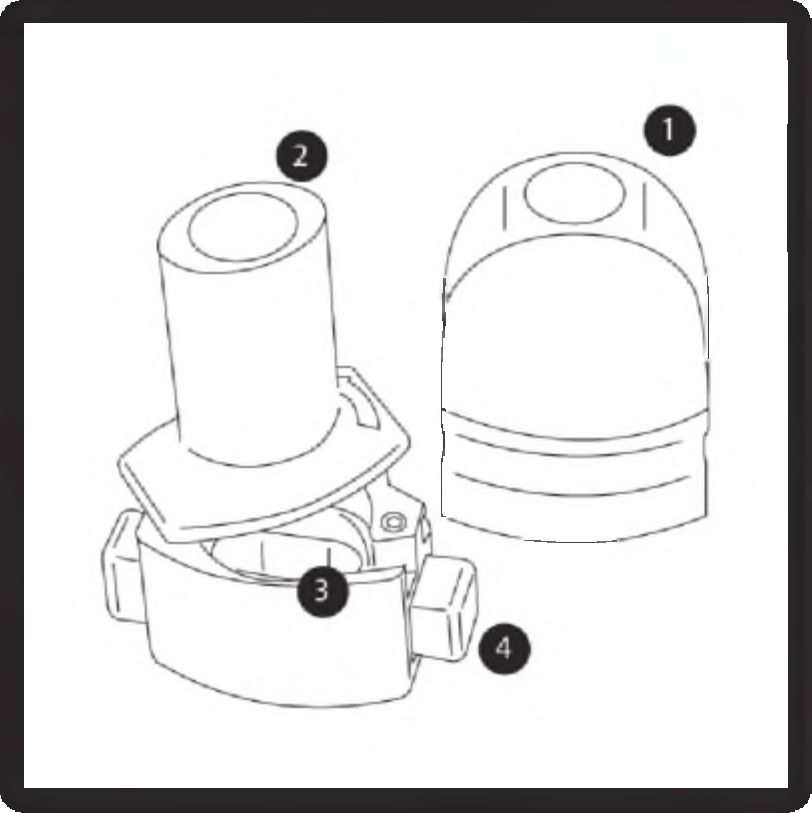

İnhalerin kısımları

1. Kapak

2. Ağızlık parçası

3. Kapsül haznesi

4. Delme düğmesi